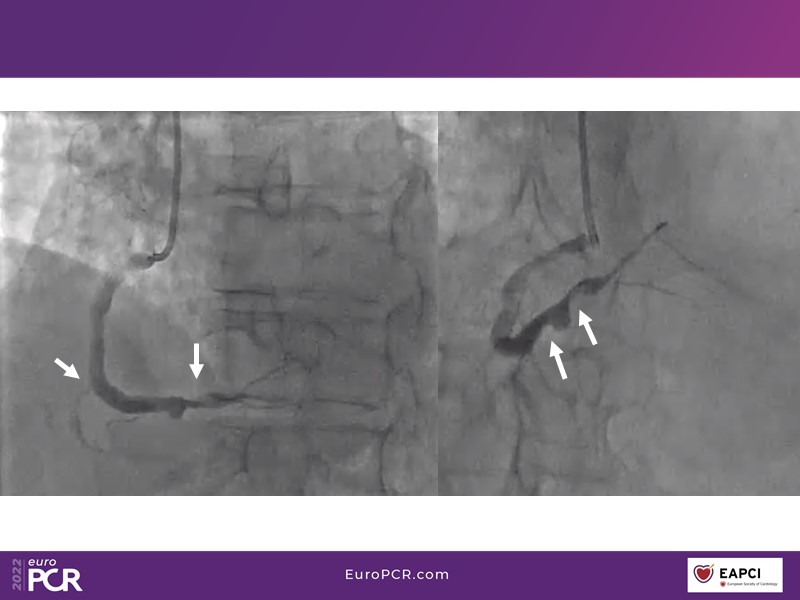

Alexandre Abizaid, Marco Valgimigli, Fazila Malik, Luca Testa, Patrick W. Serruys, Damiano Regazzoli, Kumar Prathap, and Sandeep Basavarajaiah take turns in this session to discuss two innovative technologies: a stent platform with nanotechnology and a novel drug-coated balloon (DCB). These novel technologies both have unique features that could change daily practice and improve outcomes.

- To find out more about the application and mechanism of a sirolimus coated balloon for coronary artery disease treatment with case presentations in complex settings